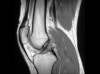

MRI는 전방십자인대 손상의 객관적인 진단 뿐 아니라 손상의 정도와 양상을 평가할 수 있고, 동반 손상을 진단하는데 매우 유용하여 치료방침 결정에 도움을 줄 수 있습니다.

MRI : 전방 십자인대 손상(ACL injury, ACL tear)